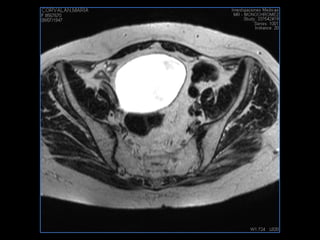

PROTOCOLO pelvis SAG T2, Y FAT SAT (FINOS) AXIAL T1  AX FAT SAT CON   GADOLINIO :  AX T1 Y COR T1 SAT: NO  FASE: RL THK: 3MM  COIL:  GAP: (FACTOR 1.4) 1MM FOV: 40 CM NEX:2 SINCRONIZACION RESPIRATORIA EN 3 O 4 CICLOS ALE